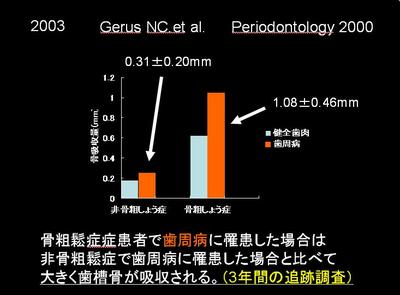

2003年Gerus先生たちは、P2000より骨粗しょう症の場合、

骨粗しょう症でない場合と比較すると

3倍以上の骨喪失を起こしてしまうデータになっています。

歯周炎の治療にもさることながら、補綴的にも

場合によってはインプラント治療にも不利になる可能性があると思われます。